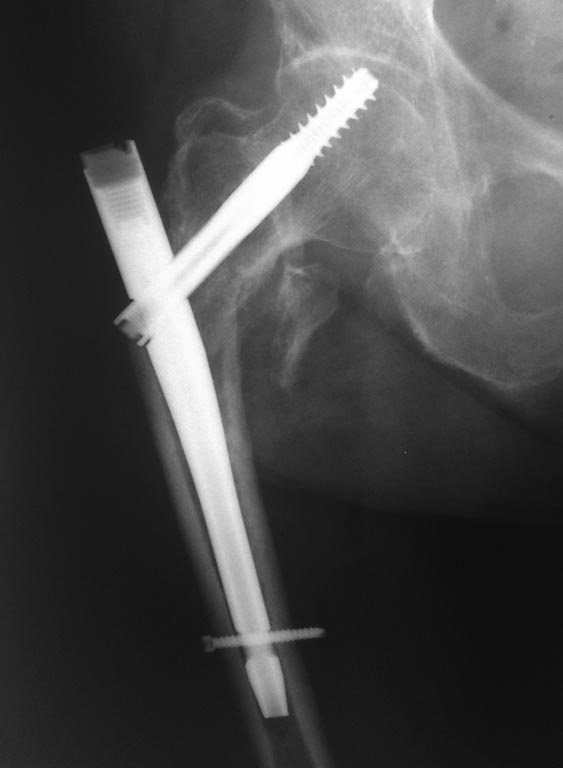

Пациентка В., 75 лет, без выраженной коморбидности, получила травму в

августе 2014 года, диагностирован "Закрытый чрезвертельный перелом

правой бедренной кости со смещением отломков", была прооперирована,

выполнена закрытая репозиция, интрамедуллярный остеосинтез правой

бедренной кости проксимальным бедренным штифтом.

К сожалению, первичных снимков не предоставлено, имеются 2 снимка, через

1 месяц после операции, в сентябре 2014 и второй снимок, в январе 2015,

пациентка на данный момент передвигается с помощью ходунков, отмечает

болезненность при движениях и пальпации, объясняет -

"Как-будто кость упирается в железку". Не хочется говорить о

неправильной технике и cut-out и/или cut-through синдроме, интересно -

что можно сделать и какую тактику лечения выбрать.